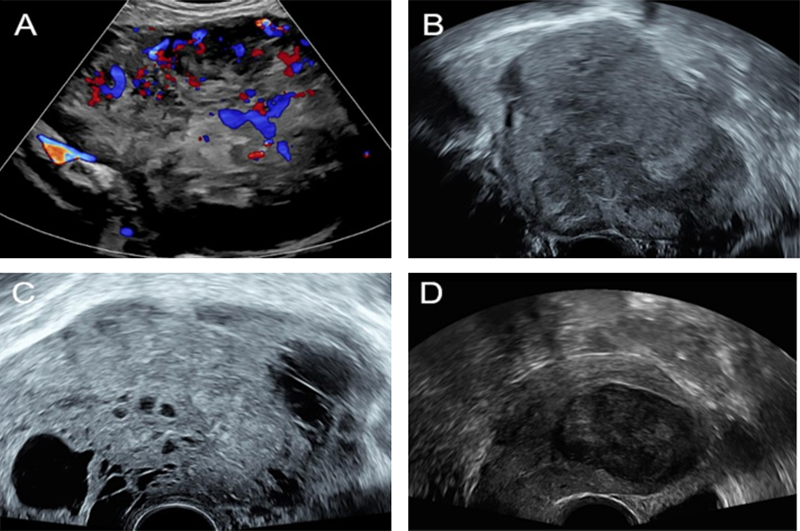

[그림1] 자궁 육종의 초음파 소견. (A. 고혈류, B. 불규칙한 경계, C. 중심부 괴사, D. 단일 타원형 종괴)